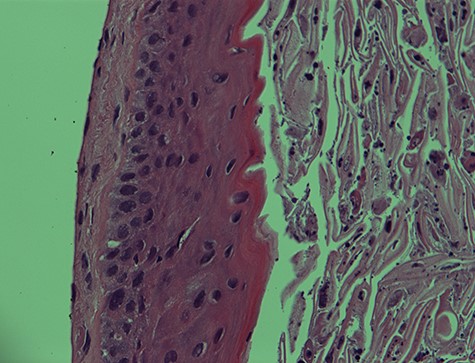

I. Epidermal cyst—400× magnification. EIC of the vocal cord. Note the undulating lining squamous epithelium with numerous keratinous and cellular debris in the lumen. H&E stain X400.

The histopathological features of the right vocal cord cyst were consistent with an EIC of the larynx, whereas the left vocal cord cyst showed minute fragment of benign squamous epithelium and skeletal muscle (Figs 1 and 2).

Both right and left vocal cord cysts were negative for dysplasia and malignancy.